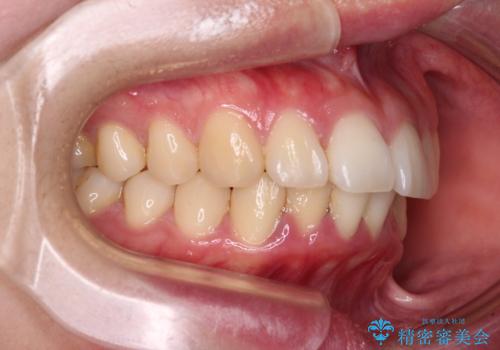

飛び出した上顎前歯 抜歯矯正でスッキリとした横顔に

- 下唇に跡がつくほどに飛び出した上顎前歯を気にして来院された患者様です。

順調に治療が進み、2年弱で想定していたとおりの仕上がりにて治療を終えることができました。